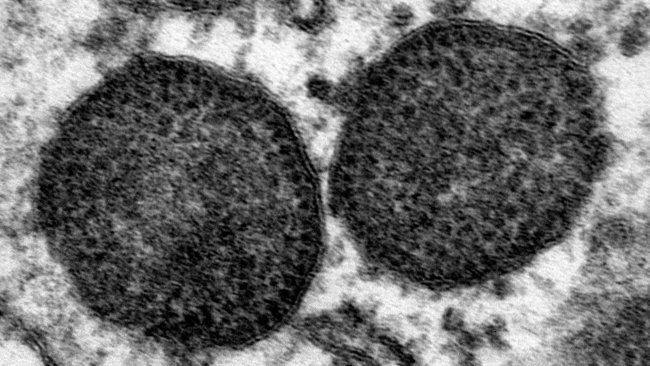

Il circovirus suino 2 (PCV-2) è una delle infezioni virali più frequenti nei suini, causando un notevole impatto economico a causa dei costi diretti e indiretti del suo controllo. Come altri virus ssDNA, il PCV-2 è caratterizzato da un alto tasso di evoluzione, che porta alla comparsa di un gran numero di varianti con differenti caratteristiche biologiche ed epidemiologiche. Nel corso del tempo, sono stati fatti diversi tentativi per organizzare l'eterogeneità genetica di PCV-2 in genotipi riconosciuti. Questa categorizzazione ha chiaramente semplificato le indagini epidemiologiche, consentendo l'identificazione di diversi modelli spaziali e temporali tra i genotipi. Inoltre, è stata sollevata l'ipotesi della virulenza variabile e dell'efficacia del vaccino. Tuttavia, il rapido aumento dell'attività di sequenziamento, insieme all'elevata variabilità virale di per sé, ha messo in discussione la nomenclatura precedentemente stabilita, portando alla definizione di diversi genotipi specifici per gli studi e ostacolando la capacità di effettuare studi epidemiologici comparabili.